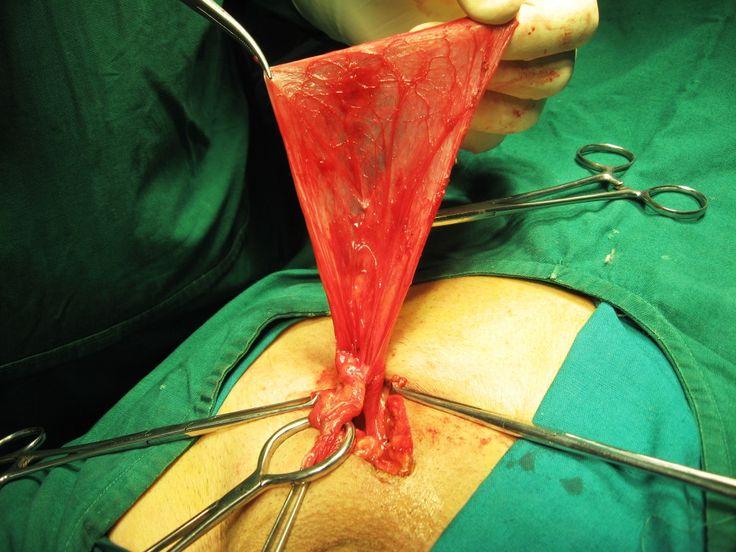

What muscle that subdivides the ventral body cavity?

contains urinary bladder, reproductive organs, and rectum name the muscle that subdivides the ventral body cavity diaphragm which organ system would not be represented in any of the body cavities

Function. These cavities contain and protect delicate internal organs, and the ventral cavity allows for significant changes in the size and shape of the organs as they perform their functions. Anatomical structures are often described in terms of the cavity in which they reside.